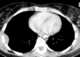

Pleural mass